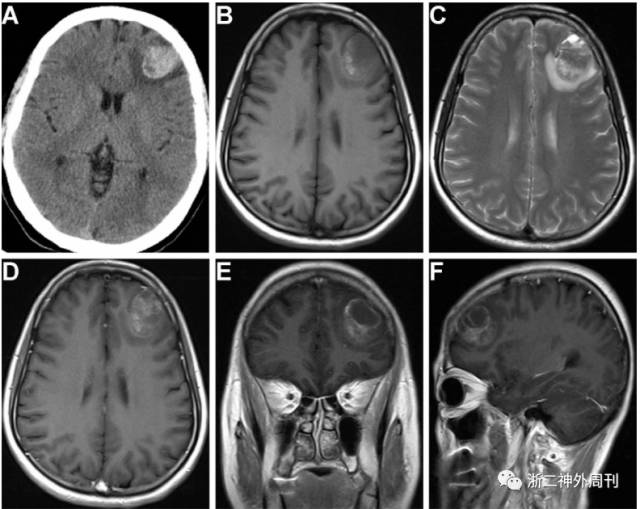

(1) 当地医院头部CT(图1-A):左额叶3.5×2.2cm大小高密度结节影,周围片状水肿带。提示出血性病灶,肿瘤可能。

(2) 我院头部增强磁共振(图1-B~F):左侧额叶见3.6×2.7cm异常信号,T1、T2加权像见高低混杂信号,见多发液平面,增强扫描见不均匀强化,考虑左侧额叶肿瘤伴出血。

图1. 头颅CT示左额叶高密度异常信号影(A);头颅磁共振平扫T1(B)、T2(C)加权像示左额高低混杂信号;头颅磁共振增强扫描轴位(D)、冠状位(E)、矢状位(F)像提示左额肿瘤伴出血。